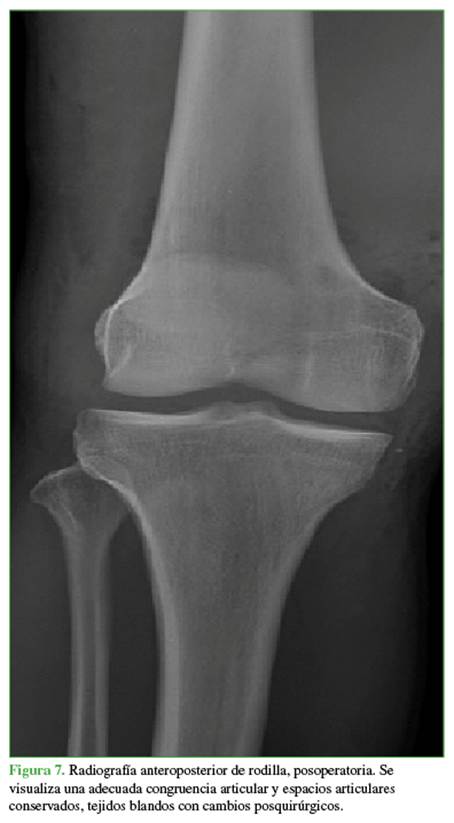

Se efectuó un abordaje medial longitudinal y se liberó el mecanismo extensor para evaluar la superficie articular de la rótula y aumentar la exposición. Se halló el cóndilo medial femoral completamente denudado. Se realizaron cuidadosas disecciones de colgajos para mejorar la visualización a pesar de tener la rótula evertida. Mediante maniobras de valgo, se identificaron y localizaron las estructuras pertinentes. Se intentó retirar el menisco, el retináculo medial y la cápsula interpuesta utilizando fuerza de palanca con diferentes instrumentos, pero no se logró, pese a las maniobras de reducción por la tensión de estas. Por lo tanto, se decidió seccionar la cápsula y el ligamento rotulofemoral para liberar el espacio femorotibial e intercondíleo, logrando así una reducción y una congruencia clínicas de la rodilla. Se procedió al lavado con abundante solución salina y, a continuación, a la rafia capsular y la sutura del ligamento rotulofemoral medial y el retináculo medial de la rodilla. Se evaluó nuevamente la estabilidad y la rodilla no se luxó con flexión profunda ni extensión, no había lesiones condrales en la rótula o en la tróclea, el menisco medial estaba pinzado, pero sin lesiones en el cuerpo o en la raíz, por lo que no requirió manejo adicional. Se colocó una férula articulada de rodilla, se solicitaron radiografías de control posoperatorio (Figura 7) y se programó una reconstrucción ligamentaria diferida a las 3 semanas en la que se reconstruyó el ligamento cruzado anterior con aloinjerto, el ligamento cruzado posterior con técnica de un solo haz con aloinjerto y la esquina posteromedial con técnica de Laprade A las 4 semanas de seguimiento, los arcos de movilidad eran de 10° a 90° de flexión de rodilla. Continúa con terapia física.